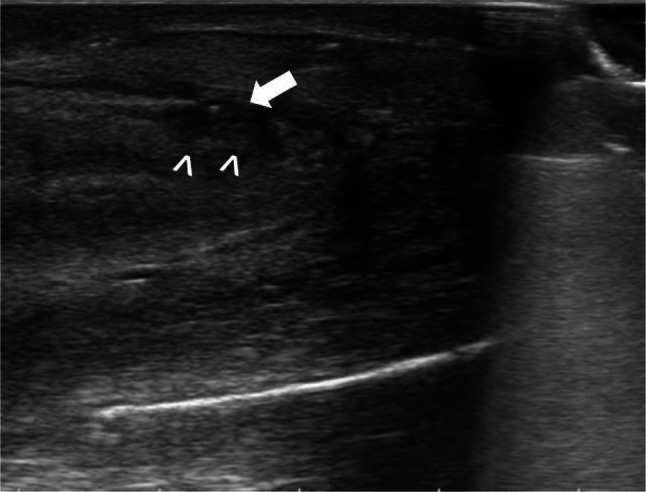

Fig. 1.

Grayscale US shows hypoechoic area in the dorsal side of CC (arrowhead) with interruption of the tunica albuginea (arrow) suspected of phlogosic intracavernous reaction